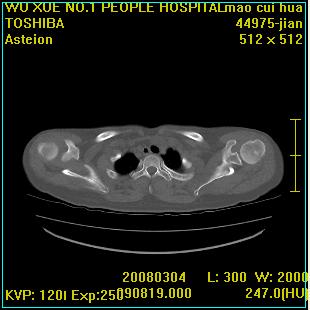

标题: CT12025:男,50岁,左肩活动受限半年。 [打印本页]

标题: CT12025:男,50岁,左肩活动受限半年。

肩关节骨质破坏呈小囊状,其周软组织轻度肿胀,余未见异常。

考虑:肩袖损伤。建议mri。

左侧肱骨头密度不均匀,高低混杂,周围软组织略肿胀,考虑结核性病变。

左侧肱骨头密度不均匀,高低混杂,髓腔密度稍高,周围软组织略肿胀,肌间隙模糊,考虑慢性骨髓炎可能。密切结合临床!

肩关节周围软组织轻度肿胀,肌间隙模糊,余未见异常。

考虑:肩周炎。